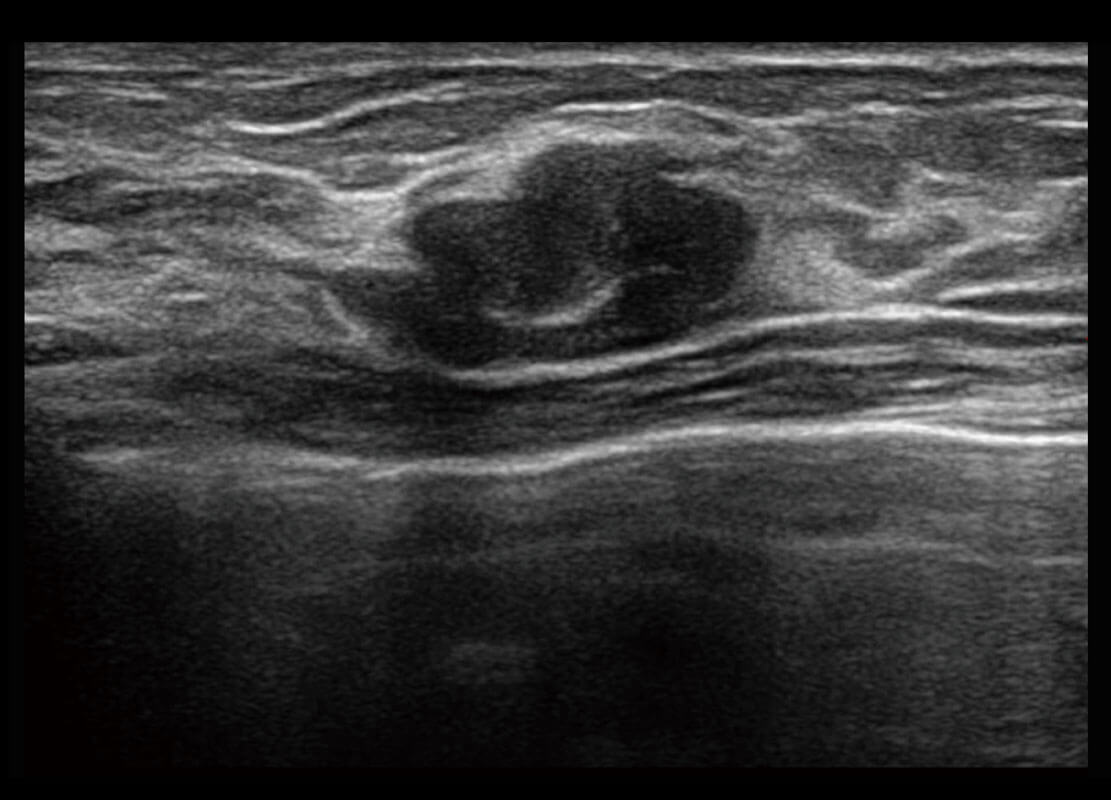

P60搭載寬頻帶線陣探頭、寬景成像、彈性成像技術(shù),為您提供乳腺應(yīng)用方案。P60支持高頻相控陣探頭、線陣探頭、腹部高頻探頭、腹部微凸探頭等,豐富的探頭群搭載敏感的彩色血流成像,適用于新生兒多種臟器檢測(cè)要求,滿足新生兒篩查需求。

乳腺導(dǎo)管癌